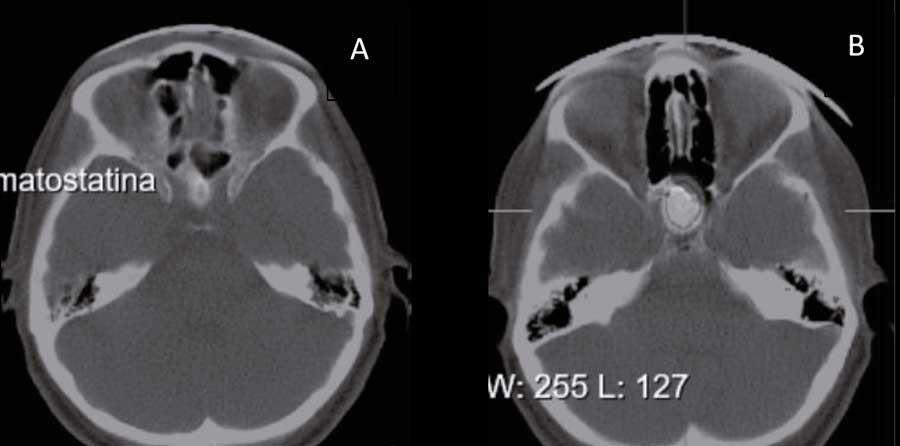

A los 5 meses, la RM de control objetiva cambios postquirúrgicos sin poder descartar restos tumorales. Una gammagrafía con receptores de somatostatina 99mTc muestra una hipercaptación focal de intensidad superior a la esperable para la actividad fisiológica normal hipofisaria en la región del seno esfenoidal, anterior e inferior a hipófisis, donde se ubicaba el EPA, pudiendo corresponder a restos tumorales (Figura 2).